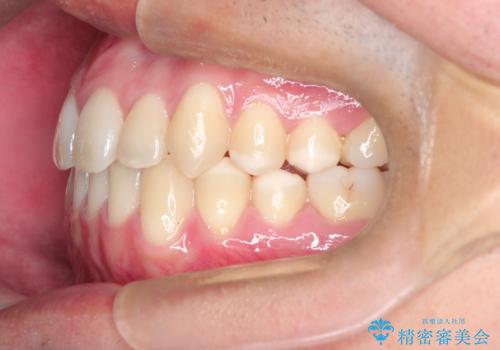

【MSE+インビザライン】前歯のガタガタ

上の歯のアーチが狭窄していたため、骨の幅を広くするためにMSE(急速拡大装置)を使用してからインビザライン にて治療を行いました。

MSE(急速拡大装置)を用いたことで、短期間で奥歯の噛み合わせもしっかりと治すことができました。